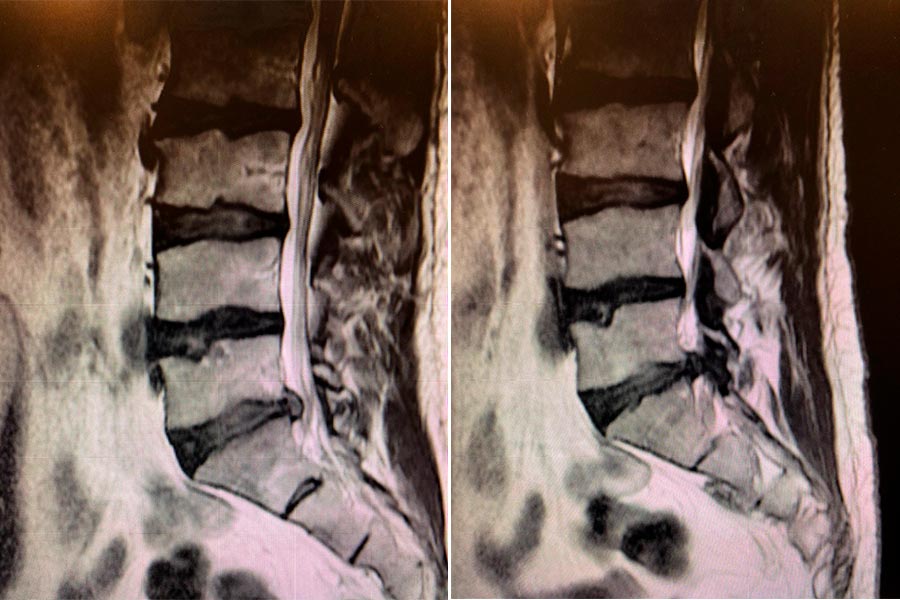

Caso clínico: endoscopia de columna multinivel L4L5 y L5S1

Los síntomas que presentaba el paciente eran dolores acentuados en las piernas, claudicación a la marcha y calambres y hormigueos en las piernas.

Durante la intervención quirúrgica, se abordarán los dos niveles mediante la técnica de endoscopia de columna.